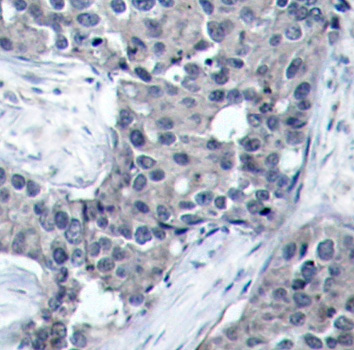

• AP0228: image 2

Immunohistochemical analysis of paraffin-embedded human breast carcinoma tissue using Phospho-EIF4E-S209 antibody.